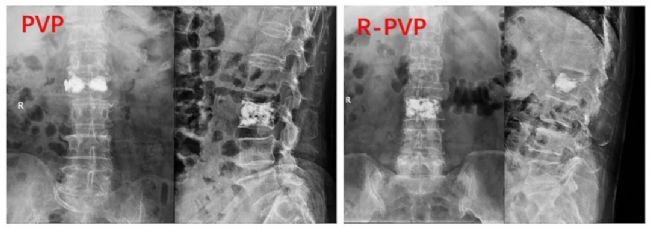

④兩組之間骨水泥彌散的程度:使用ImageJ軟件評估骨水泥的彌散程度,結(jié)果分為四類:I度代表骨水泥在正側(cè)位片上的覆蓋面積均小于50%;Ⅱ度代表骨水泥在正位或側(cè)位片上的覆蓋面積大于50%小于75%;Ⅲ度代表骨水泥在正側(cè)位片上的覆蓋面積均大于50%小于75%;IV代表骨水泥在正側(cè)位片上的覆蓋面積均超過75%,兩組間差異有統(tǒng)計學意義。

術(shù)后X線顯示骨水泥的彌散。與PVP組相比,R-PVP組在術(shù)后X線片上表現(xiàn)出更強的在椎體中線的融合能力。